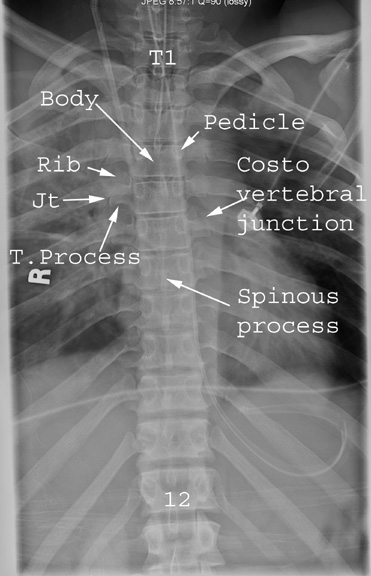

Identify the parts seen. Click the image for labeling.